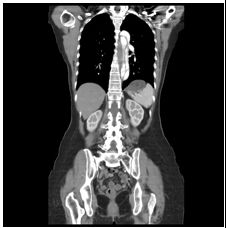

3. 病人18歲女計程車無線呼叫員, 到院主訴有五天的間 歇性燒熱及寒顫(chillness), 並合併頭痛、雙眼後疼痛及全身肌疼, 經初步診斷腦膜炎, 病人拒絕腰椎穿刺檢查, 乃試用抗生素後回家療養。 唯症狀仍舊, 尚有噁心、嘔吐, 並先後在左大拇指及右小趾出現疼痛紅斑(如圖A及B所示)。既往病史有二尖瓣膜脫垂及閉鎖不全。理學所見身高:162cm;體重:45Kg;BP:105/67mmgHg;T/P/R: 39.8C/155/18。未見Meningeal signs. 頸部末見異常, 心尖在left 5th ICS, mid-clavicular line, 有Grade III/VI Pansystolic murmur. S1及S2正常。胸、腹都無不正常。實驗室檢查: WBC:4.39x k/uL,有left shifting;RBC:5.12 x M/uL;Hb:11.0 g/dL;Platelets:130 x K/uL;其血液細菌培養結果如與胸部X光詳見附圖C、D。心電圖如附。本病人經過下列臨床處置